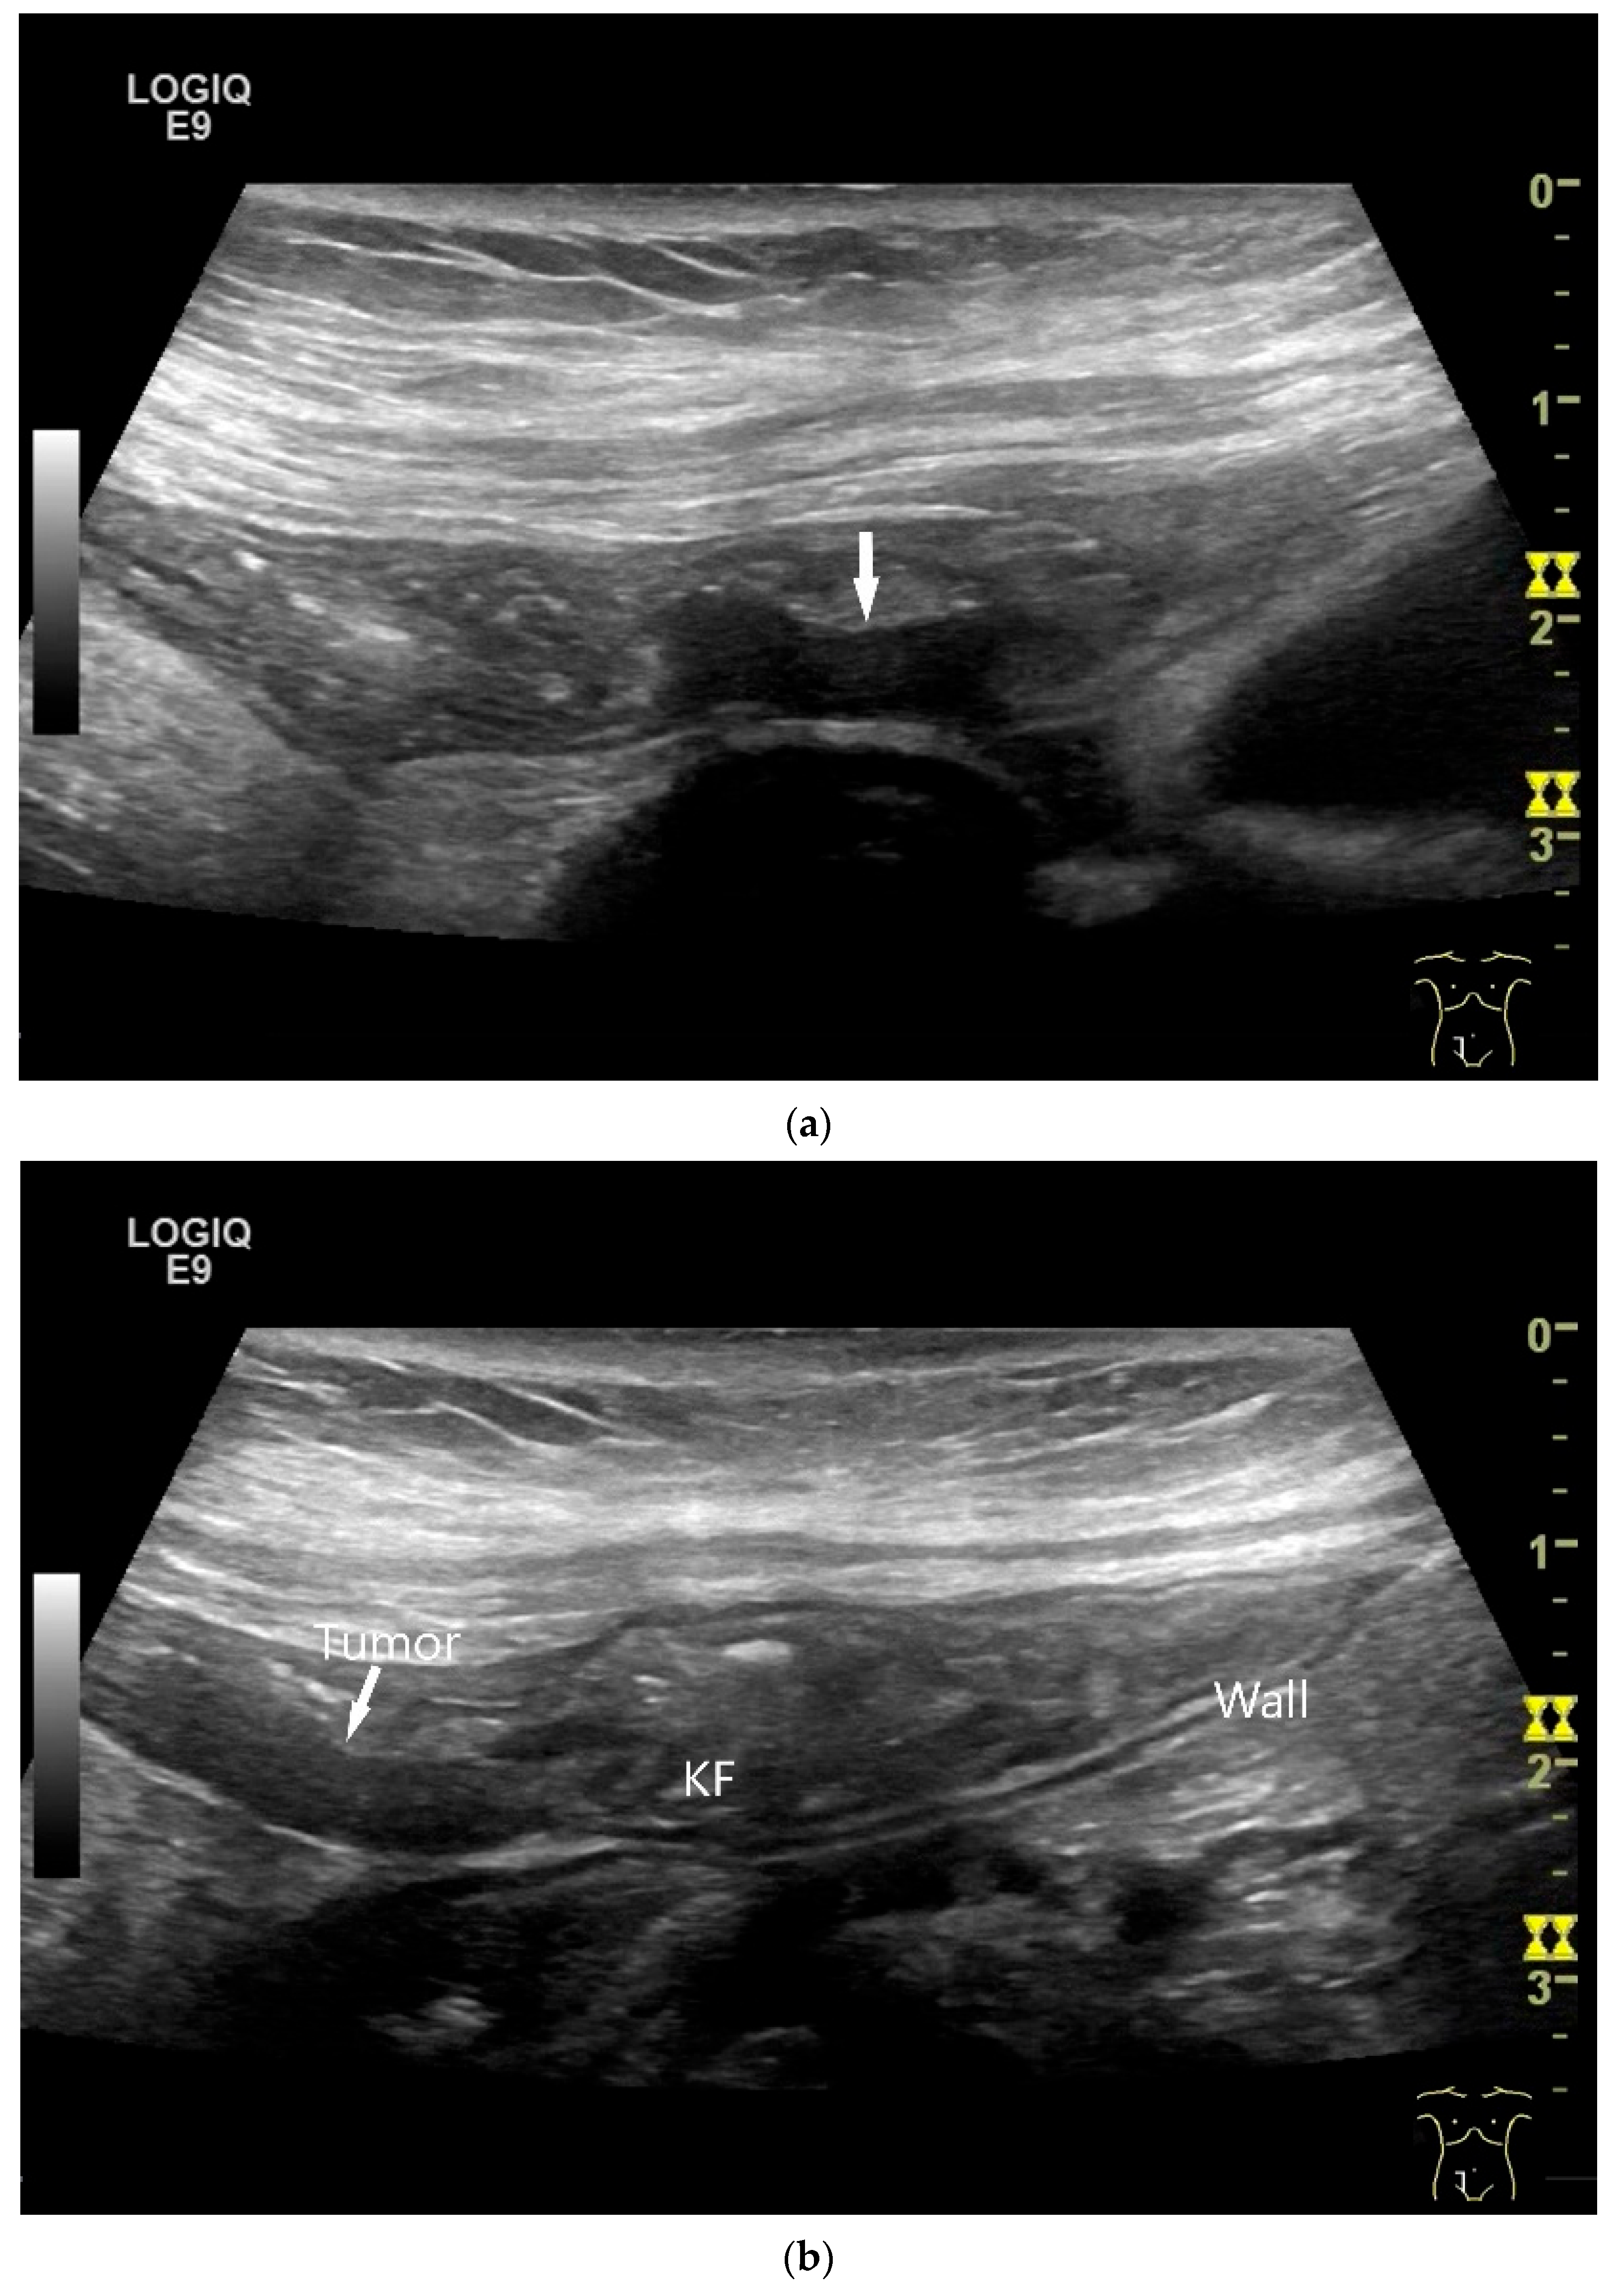

| Intussusception | The small intestine proximal to the tumor is invaginated. More than five wall layers are seen in an onion-skin shape. |

| Proximal to the tumor | Dilated small bowel lumen, possibly hypertrophy of the muscle layer and hyperperistalsis of this bowel segment |

| Neuroendocrine tumor | Small, nodular hypoechoic wall thickenings, mostly in the submucosa with spreading into the other layers. Usually with small vessels on CDI. Regionally enlarged lymph nodes. Multilocular manifestations are possible. |